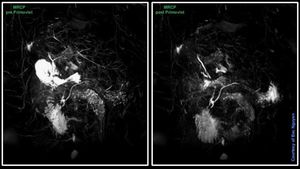

To do, or not to do…… This image shows the Primovist/Eovist effect when doing MRCP after given this agent, you get signal drop in the biliary system. Some paper says you are safe within 3-5min by doing MRCP after given this contrast. Some recommend not to do MRCP as post contrast. Personally, I strongly advice not to, a lot of things can go wrong by doing it post contrast. What if patient have an inconsistent breathing pattern, and you need to redo the scan… well time have already passed and you too late then. Really, what do you save in time by doing MRCP as post contrast? I guess not much. Because in the waiting period of hepatobiliary phase (20min post contrast) you already used some time from the dynamic, and can carry on with a good DWI + 2D/3D TSE FS. This will fill your time perfectly and you’re much safer with pre MRCP.#Siemens_MRI #siemens #mri #primovist #gadolinium #abdominal_liver